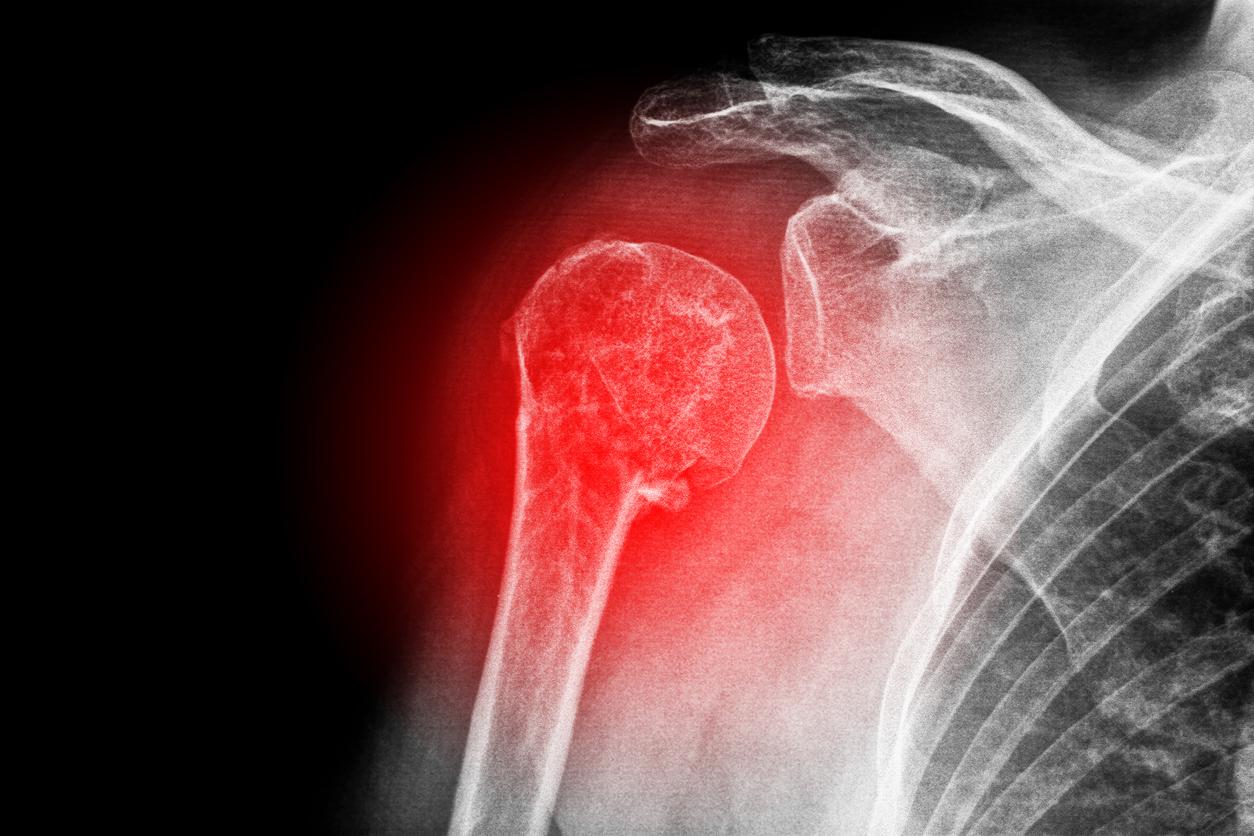

Maladie osseuse souvent qualifiée de "silencieuse", l'ostéoporose se manifeste généralement chez certaines personnes âgées de plus de 50 ans, en particulier les femmes. Toutefois, elle est rarement détectée à temps ; par exemple, si une femme de 65 ans glisse et se casse l'épaule – aussi appelée l'humérus – la piste de l'ostéoporose ne sera pas systématiquement explorée. "Ce n’est pas normal de se casser de sa hauteur : il faut suspecter une fragilité osseuse", alerte auprès de Pourquoi docteur la professeure Karine Briot, rhumatologue à l'hôpital Cochin, à Paris.

La professionnelle de santé est catégorique : normalement, l’os de l’humérus est résistant à un traumatisme équivalent à une chute de sa hauteur. Ainsi, en cas de fracture de l’épaule alors que l’on est tombé en marchant ou en glissant, il convient de consulter son médecin, d’évoquer l’ostéoporose, et de demander à passer une ostéodensitométrie. "C’est un examen qui mesure la résistance osseuse, la qualité et la quantité d'os, reprend l'experte. Cela permettra de dire s’il y a une fragilité osseuse ; c’est indispensable".

En plus de poser le diagnostic de l'ostéoporose, la densitométrie osseuse permet de prédire le risque de nouvelles fractures, notamment du col du fémur, des vertèbres, de l’humérus et du bassin. "Le risque est augmenté à deux ans", assure la docteure Karine Briot, en précisant que la fracture de l'humérus multiplie par trois à quatre le risque de se casser le col du fémur dans les années suivantes. Concrètement, cela signifie que, si l'on veut réellement prévenir la deuxième fracture, il faut réaliser une ostéodensitométrie dans les mois, voire les semaines, qui suivent la première.

En dehors de l'ostéoporose, il est possible que l'examen révèle une ostéopénie, c'est-à-dire une déminéralisation osseuse modérée, qui peut évoluer vers l'ostéoporose si elle n'est pas corrigée. "Des os comme le col du fémur, l'humérus, une vertèbre et le bassin sont vraiment très résistants : même si la densité osseuse n'est pas très abaissée et dans les seuils de l'ostéopénie, il faut tenir compte de l'antécédant de fracture et se poser quand même la question de traiter la fragilité osseuse", explique la rhumatologue.